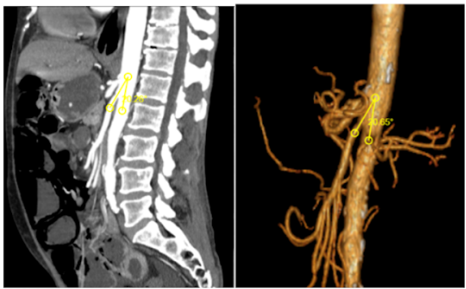

Initially, x-ray findings show gastric or gastroduodenal distention and a paucity of distal bowel gas [5]. Later, tomographic images include compression of the third part of the duodenum with proximal dilatation of the same and the duodenum. Through a deeper review of the literature, we found the normal parameters needed to take into consideration in the images’ review. Firstly, an aortomesenteric angle between 25°-60° and secondly, a distance between the AA and the SMA of 10 to 20 mm. In sagittal slices, Wilkie’s syndrome is defined as an aortomesenteric angle less than 22° (Figure 1) and in axial slices an aortomesenteric distance less than 10 mm (Figure 2) [2,5]. CT angiography provides the added benefit of thin (1-mm) slice thickness and multiplanar 3D reconstructions which allow for more precise evaluation of the aorto-mesenteric angle and aortomesenteric distance [5].

Figure 2. CT with IV contrast, sagittal section and 3D reconstruction showing a reduced aorto-mesenteric angle of 20°.